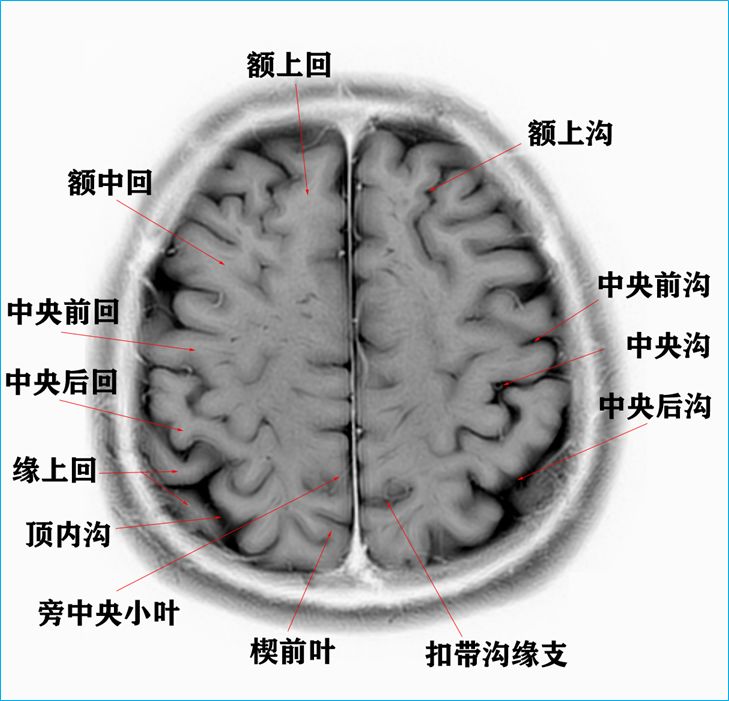

在T2WI反相下的颅脑断层解剖以及标本断层解剖.

3.0T-T2WI反相图学颅脑断层解剖

大脑半球标本连续切片断层解剖

在T2WI反相图学下的颅脑断层解剖(吴老师亲自手动标准)以及标本断层解剖

作者:吴晓安 仅供学习交流